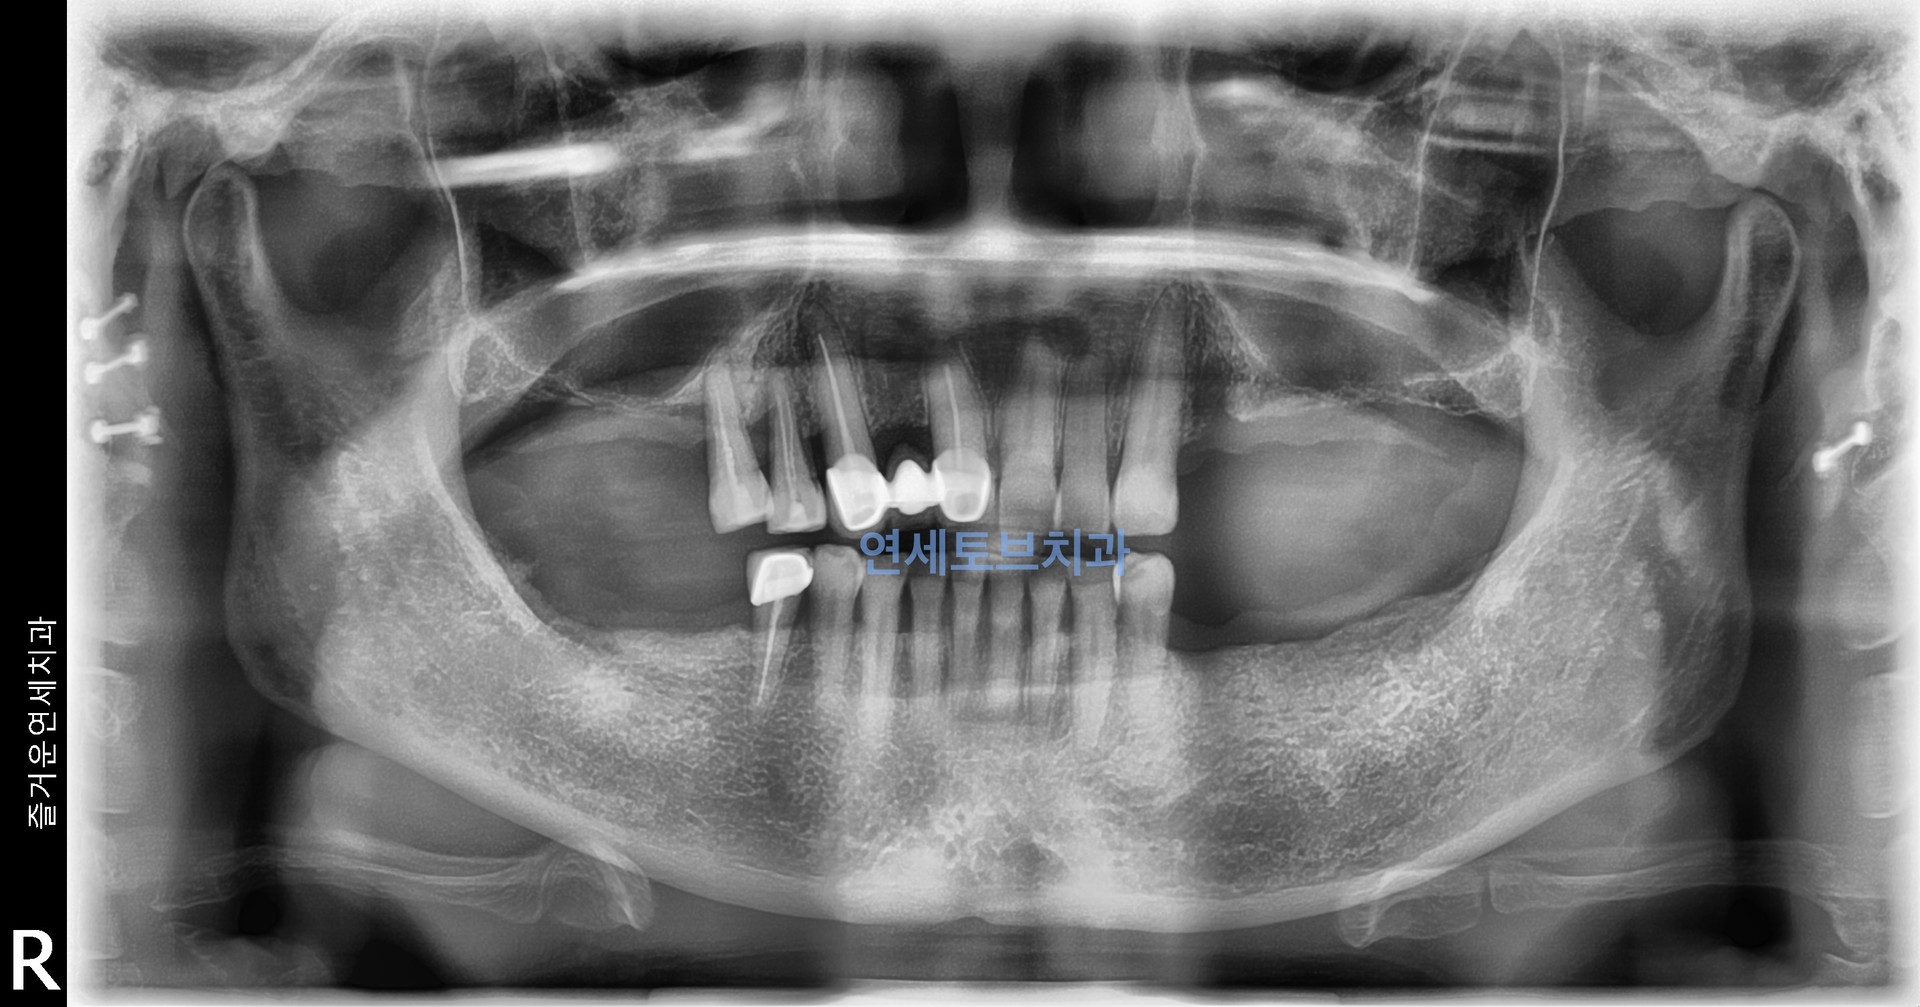

#1

상악동 골이식술은 상악 어금니 부위 임플란트 식립에 필수적인 뼈를 확보하는 신뢰도 높은 술식으로, 치조골이 부족한 환자에게 임플란트의 성공률을 높여주는 중요한 수술입니다